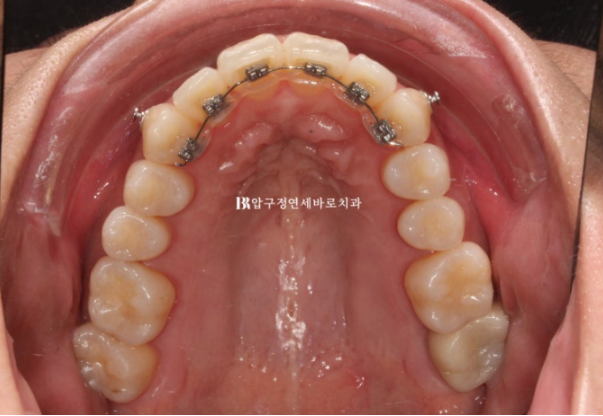

24.07 2D 설측 장치 교정

설측장치인 2D 부분교정용 장치 모습입니다.

뒤로 붙이니 교정기간 내내 보이지 않습니다.

덧니 작은어금니를 제 위치로 넣기 위해 아래는 앞니 포함 9개 치아에 MTA 장치를 붙이고 배열했습니다.